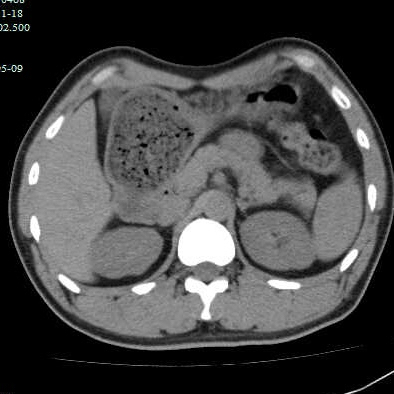

最近有几个吃山楂后形成胃结石的病历,第一个,老年女性,突发腹痛2天,持续性钝痛,阵发性加重,伴恶心,呕吐胃内容物,性状无异常,呕吐后无缓解,入院后抑酸治疗效果不理想,CT如下图。

考虑胃内结石,予以碳酸氢钠和可乐口服,第二天症状缓解,因为有别的问题,没有胃镜证实。

因为非影像专业,自己总结肠道植物性结石的特点,混杂密度,多数边缘规则,与正常胃、肠壁结构分界清晰,临床考虑多数急性起病,关键是要问近期是否有大量食用柿子、山楂、黑枣等富含鞣酸食物。